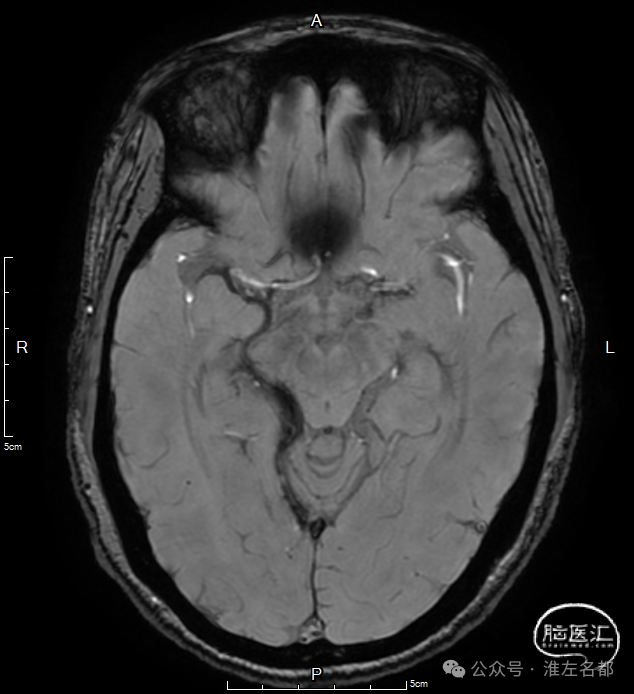

双侧丘脑和右侧内囊-间脑淤血性梗死、水肿和伴渗血。

SWI:双侧丘脑渗血改变,右侧基底静脉和大脑中静脉血栓。